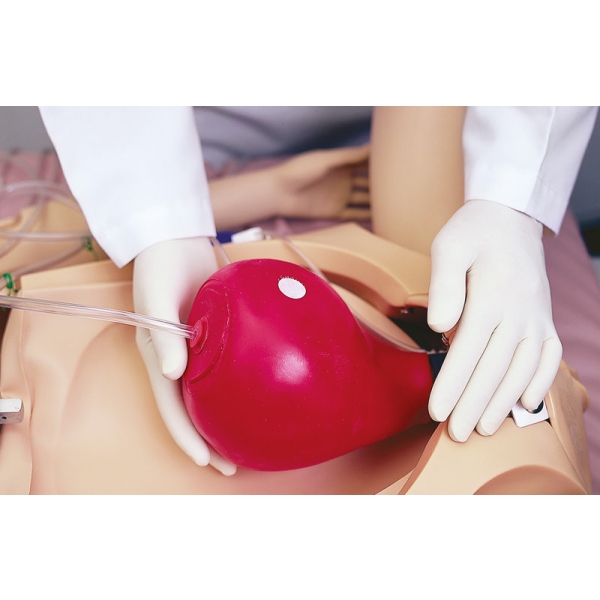

Noelle Simulator poroda mater in novorojenčkov

Zasnovan tako, da zagotavlja popolno porodno izkušnjo pred, med in po porodu.

- več lokacij posteljice

- zamenljivi dilatacijski pripomočki